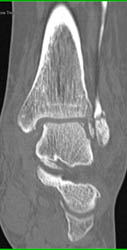

Osteomyelitis Great Toe